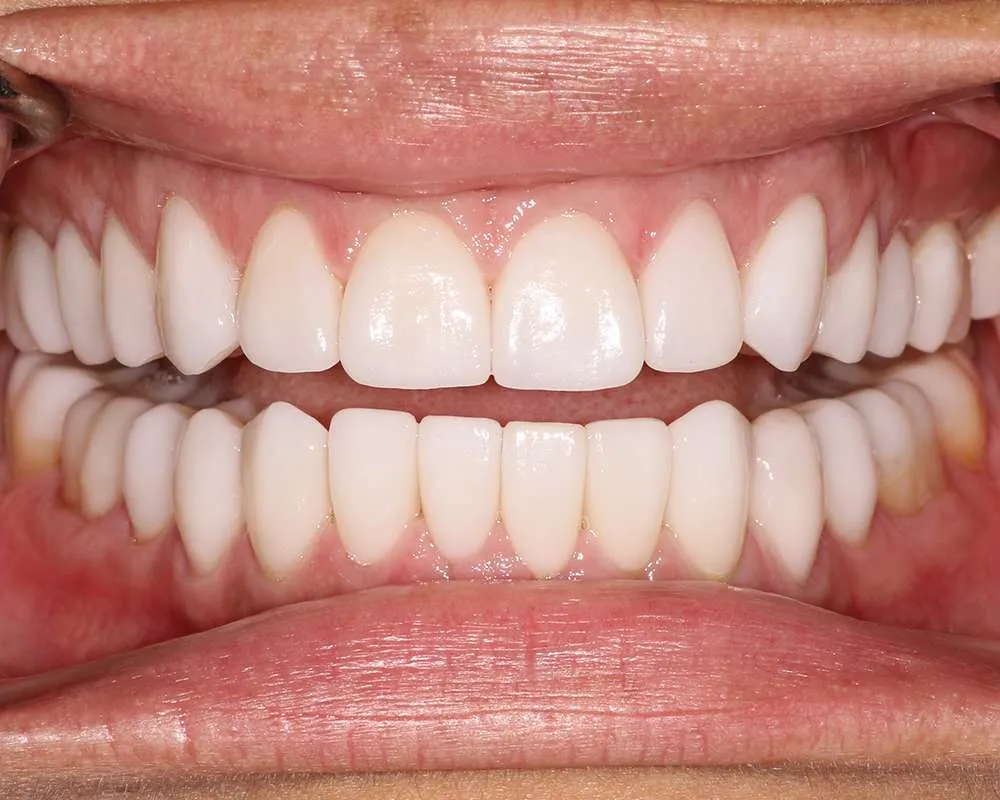

Real Stories, Real Results: Case Studies Showcasing How Our Personalized Approach Transforms Smiles and Lives

Ultra-thin veneers are crafted from high-quality materials that closely resemble the look and feel of natural teeth. The translucency and texture of these veneers mimic the appearance of real enamel, ensuring that your smile looks natural and aesthetically pleasing. Each veneer is custom-made to match the color, shape, and size of your existing teeth, blending seamlessly with your natural smile. This attention to detail ensures that your veneers are virtually indistinguishable from your natural teeth, providing you with a flawless, beautiful smile.

Complex Cases

Witness the Remarkable Changes We Can Achieve